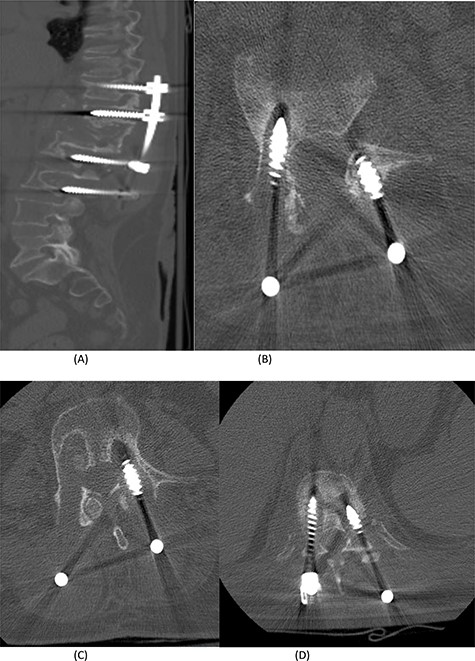

(A) Sagittal spine CT demonstrating a burst fracture involving L1 vertebral body with retropulsion of fragments and epidural soft tissue mass indenting the conus medullaris at the level of T12–L1. (B) Axial spine CT of the corresponding level of L2 vertebral body. (C) Axial spine CT of the corresponding level of L3 vertebral body. (D) Axial spine CT of the corresponding level of T11 vertebral body.

Fourteen months later, the patient presented to the ED complaining of generalized body pain associated with malaise. The neurological examination was unremarkable. An MRI of the lumbar spine showed recurrence of the lesion with loosening and pullout of the implant, kyphosis and dislocation, with cord compression and collection (Fig. 2). Computed tomography (CT) scan showed a burst fracture of the L1 vertebra with loose screws (Fig. 3). CRP was 21 mg/l, ESR was 115 mm/h and procalcitonin was 0.051 ng/ml. The decision was made to do a CT-guided biopsy from the left paraspinal mass of T12–L1. The tissue biopsy was subjected to TB-polymerase chain reaction testing and acid-fast bacillus culture; both results were positive for M. tuberculosis. The patient was diagnosed with TB spondylitis and was started on the full anti-TB four-drug regimen.